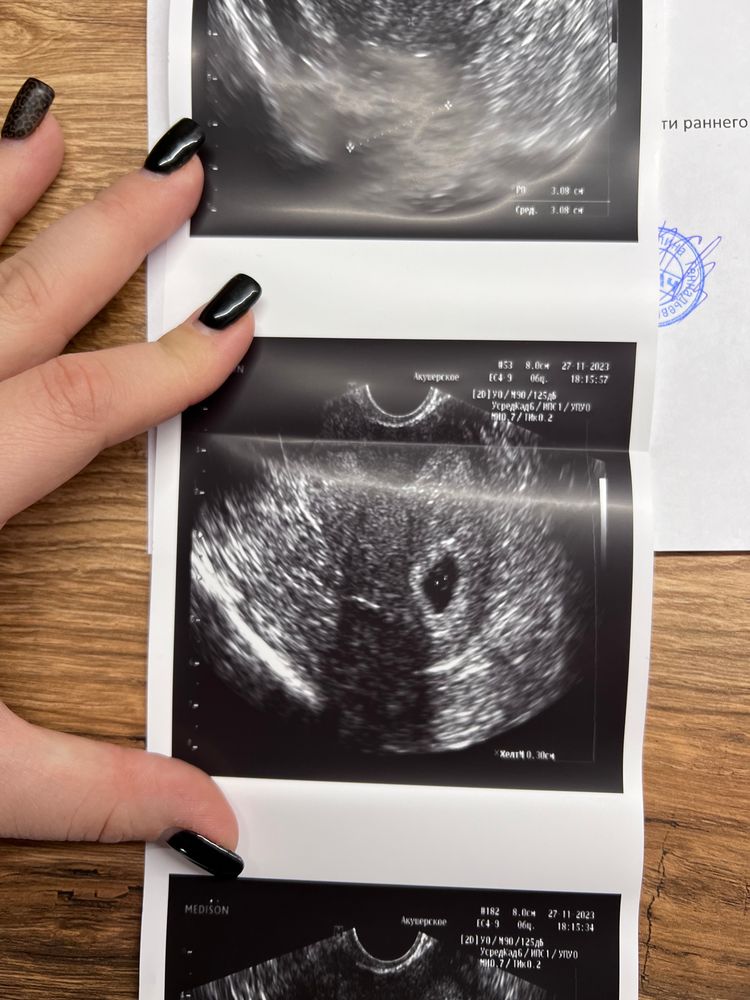

жду мальчика, 10 неделя Калининград

Выделения на раннем сроке…

Что за срок такой, 2 недели? У вас же написано 6я идет. Такое бывает, главное нет отслоек и прочего.